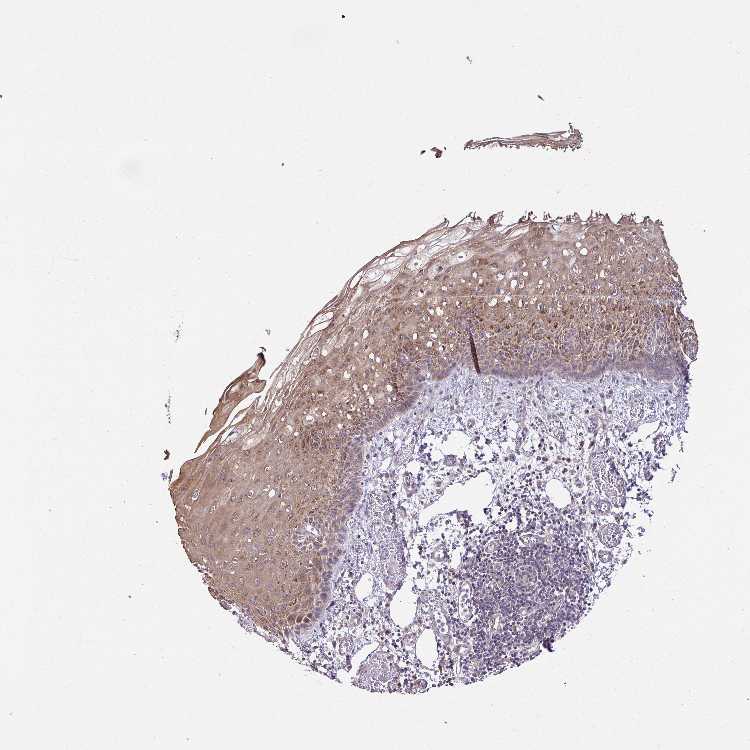

ESOPHAGUS - Antibody stainingi

Antibody staining in the annotated cell types in the current human tissue is reported as not detected, low, medium, or high, based on conventional immunohistochemistry profiling in selected tissues. This score is based on the combination of the staining intensity and fraction of stained cells.

Each image is clickable and will lead to virtual microscopy that enables deeper exploration of all samples and also displays staining intensity scores, fraction scores and subcellular localization as well as patient and tissue information for each sample.

Antibody HPA056686

Squamous epithelial cells High